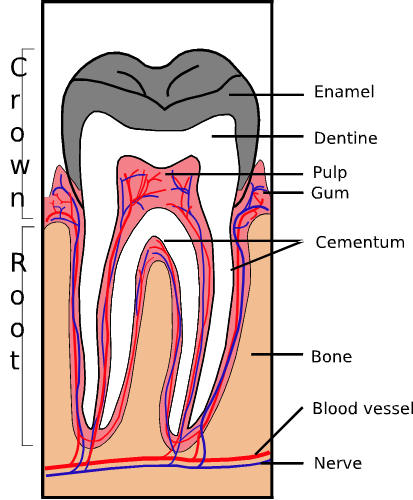

| Cross section showing parts of tooth. |

Sam Fentress, 7 June, 2005. Creative Commons Attribution Share-Alike 2.0. |